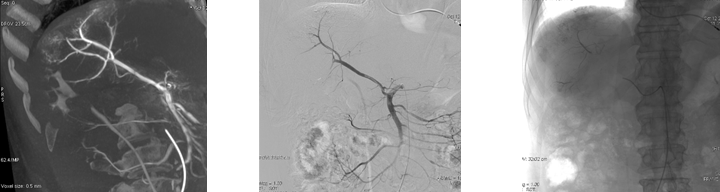

1.5s快速3D扫描,AW工作站自动重建后,可以从多角度多维度的观察肿瘤供血动脉,剔除骨骼等影响后,血管及病灶显示更清晰。

2.MIP重建下调节层厚信息,可以清楚的看出病灶的滋养动脉,辅助栓塞治疗。